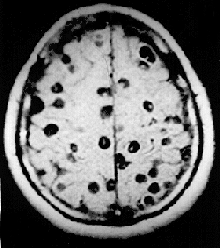

![]() صورة بالرنين المغناطيسي لشخص مصاب بداء الكيسات المذنبة العصبي تظهر العديد من الأكياس ضمن الدماغ صورة بالرنين المغناطيسي لشخص مصاب بداء الكيسات المذنبة العصبي تظهر العديد من الأكياس ضمن الدماغ | |